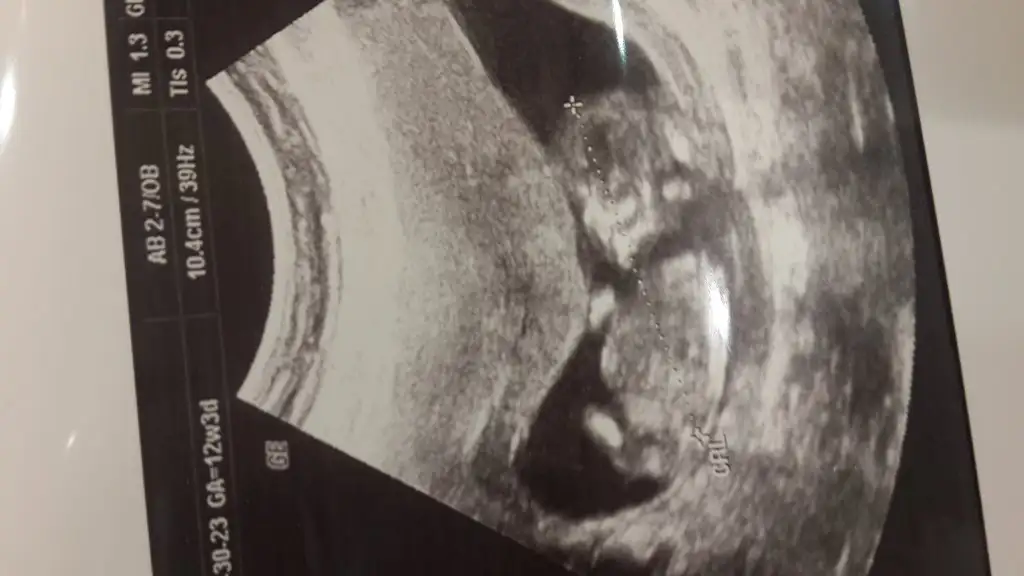

Anlamadim cabim 18 hafta ne diyo ?Doktordan geldik teyzelerimiz sma doktor illa kesin 18. Hafta diyor simdude 14+5 fotomuz varmi yorumu olan

Canim ben hep erkege benzeytim diyeyse senin bebisi doktir bise demedimi daha..Merve bide bu son halimize. Yorum yapar misin 17 haftalik